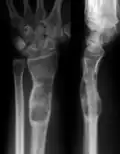

Abnormal bone growth such as shortening or thickening and deformity may be observed in patients of Ollier disease. These bone lesions are visible at birth using radiography but are usually not screened or examined for until clinical manifestations present during early childhood. However, some patients may exhibit no signs of any symptoms.[1] One study found thirteen to be the mean age of diagnosis in patients with Ollier disease. In an X-ray, there would normally be the presence of several homogeneous lesions of an oval or elongated shape with bone edges that are slightly thickened.[3] With age, these lesions may calcify and appear as diffusely minute spots or stippled. Fan-like septations or streaks would be indicative of the presence of several enchondromas. Early detection and consistent and repeated monitoring is important in order to prevent and treat any potential bone neoplasms.

X-ray showing calcified enchondromas localized in finger a 37-year-old patient affected with Ollier disease -